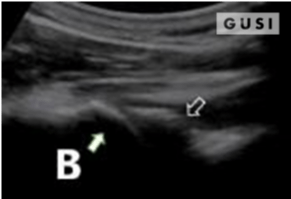

During the 2018 World Taekwondo Junior Championships in Hammamet, Tunisia, a 17-year-old male junior Taekwondo athlete took a fall, landing on his right shoulder. He exhibited a markedly limited range of motion in the affected shoulder and experienced intense pain, leading to suspicions of a dislocation.

|

|

|

|

|

A pre-reduction ultrasound (A) of the right shoulder showed a pronounced gap between the humeral head (indicated by a solid arrow) and the glenoid (marked by an open arrow), suggesting an anterior dislocation. Following a shoulder reduction procedure, a post-reduction ultrasound (B) verified the successful realignment of the glenohumeral joint (solid arrow pointing to the humeral head and open arrow to the glenoid).

After the procedure, the athlete displayed a considerably improved range of motion in his right shoulder and his pain levels diminished significantly.